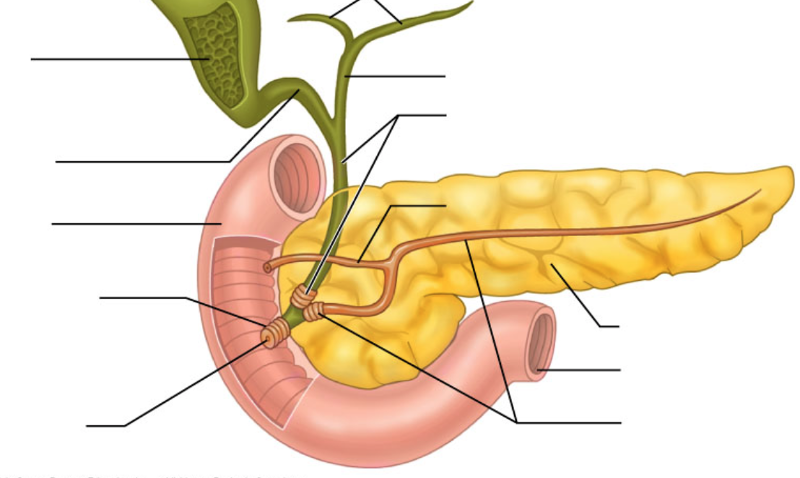

Pancreas